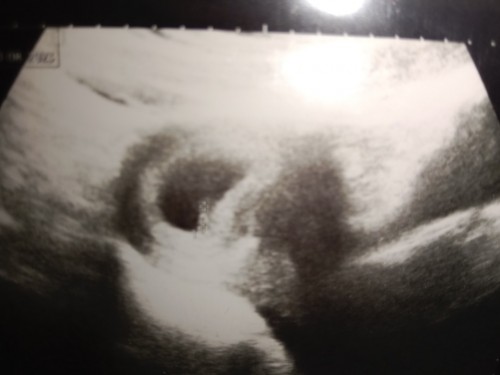

CRL 0.47 CM

ซาวด์ท้องตอน 6 สัปดาห์ แบบนี้ปกติมั้ยคะ CRL 0.47 CM

ปกตินะคะแม่